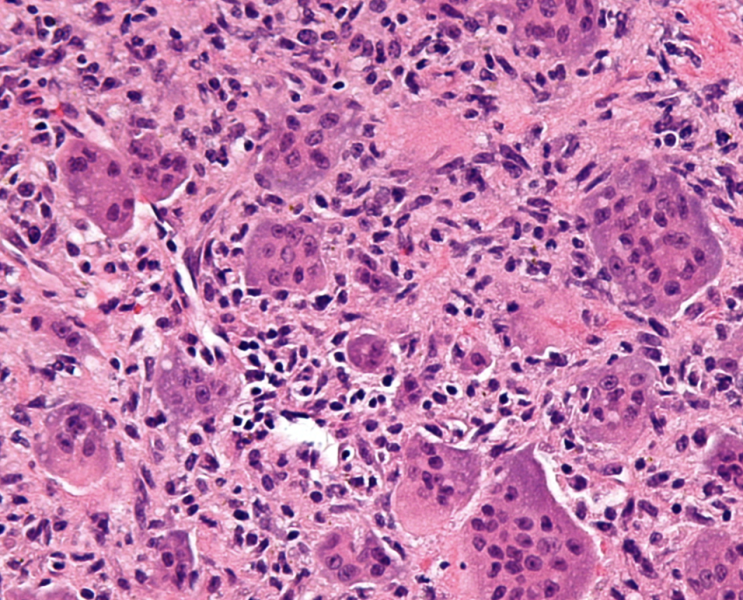

뇌 톡소플라스마증 (Cerebral Toxoplasmosis)의 병리 소견

주로 HIV와 관련된 면역억제 환자에게서 발생하는 기회 감염(opportunistic infection)입니다. 임상 증...